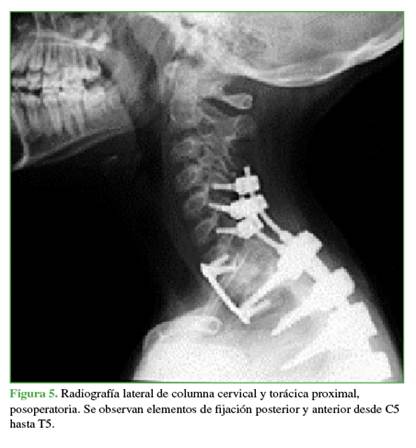

A las 48 h de la embolización, se llevó a cabo el primer tiempo quirúrgico que consistió en una instrumentación pedicular de C5-T5 con descompresión posterior de C7, T1 y T2 (Figura 5) y, también, en la resección de la masa tumoral. Durante el procedimiento, el sangrado fue de <500 ml.

Cinco días después de la cirugía, se efectuó el segundo tiempo quirúrgico que consistió en una cirugía por vía anterior para realizar una corpectomía de T1. Se utilizó aporte de injerto autólogo como soporte.